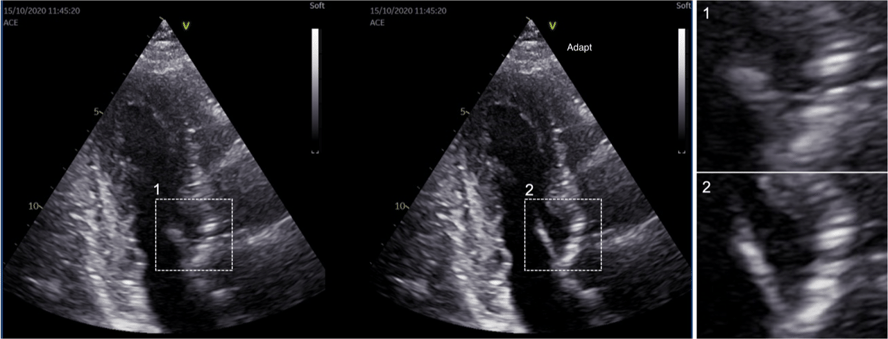

Videre arbeid med voksne pasienter har ført til nye fremskritt og nye muligheter for diagnostisering og overvåkning av hjertesykdommer. Et prosjekt i CIUS har ledet til kommersialisering av ny teknologi for å bedre bilder av hjertet. Teknologien optimaliserer bildekvaliteten på den enkelte pasient. Det er helt nytt og kan blant annet brukes til å skape detaljerte bilder av hjerteklaffenes bevegelser. Teknologien er allerede i bruk i tusenvis av systemer på verdensbasis. Dette gir legene bedre informasjon og innsikt under utredning og behandling av hjerteinfarkt eller hjertesvikt.